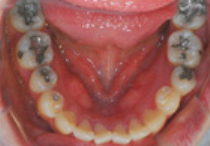

BEFORE

AFTER